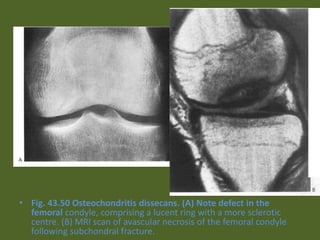

• Fig. 43.50 Osteochondritis dissecans. (A) Note defect in the

femoral condyle, comprising a lucent ring with a more sclerotic

centre. (B) MRI scan of avascular necrosis of the femoral condyle

following subchondral fracture.

• Fig. 43.50Osteochondritis dissecans. (A) Note defect in the femoral condyle, comprising a lucent ring with a more sclerotic centre. (B) MRI scan of avascular necrosis of the femoral condyle following subchondral fracture.